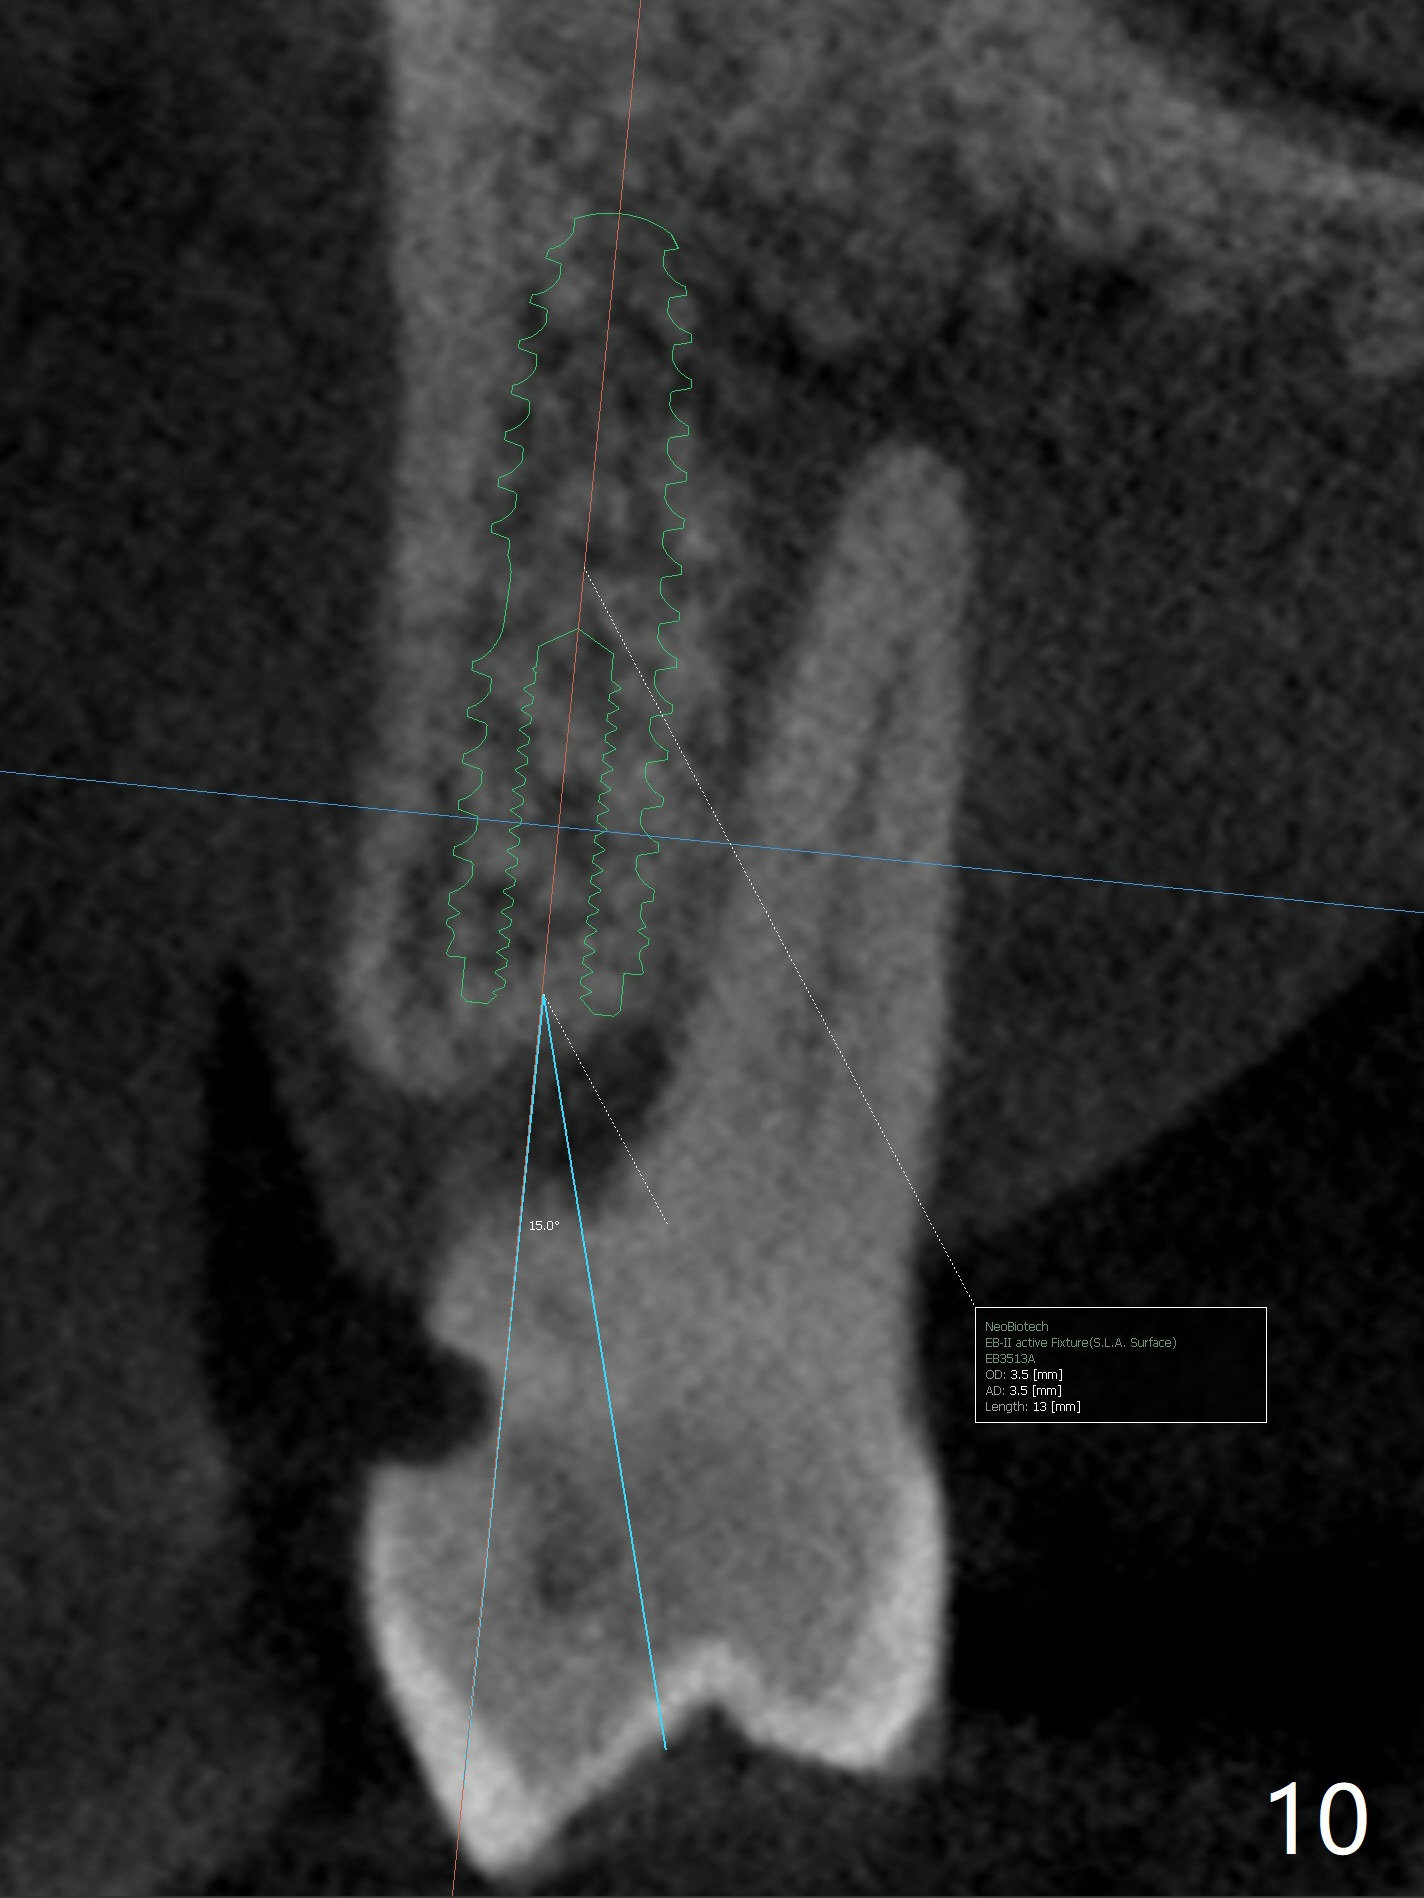

A 52-year-old man (smoker 1 ppd) has toothache in UR. The tooth #4 has severe Class V defect (Fig.1 *), periapical radio-lucency (PARL, arrow-heads) around the buccal roots and mild percu-ssion. PARL is more severe around the palatal root (Fig.2 P). Since it seems difficult to do socket preser-vation, can we do RCT to regrow bone before implant? CT coronal section shows the palatal defect of the palatal root (Fig.3,4), while sagittal one shows J defect of the palatal root, associated with root fracture (Fig.5). In fact the palatal root has transverse fracture at crestal level (Fig.6-8). The tooth #4 will be extracted for immediate implant (Fig.9,10); a 4 mm implant will be placed in the narrow space of #3 at the same time (Fig.11). The patient had symptoms consistent with aortic aneurysm. Since then smoke has been quit.